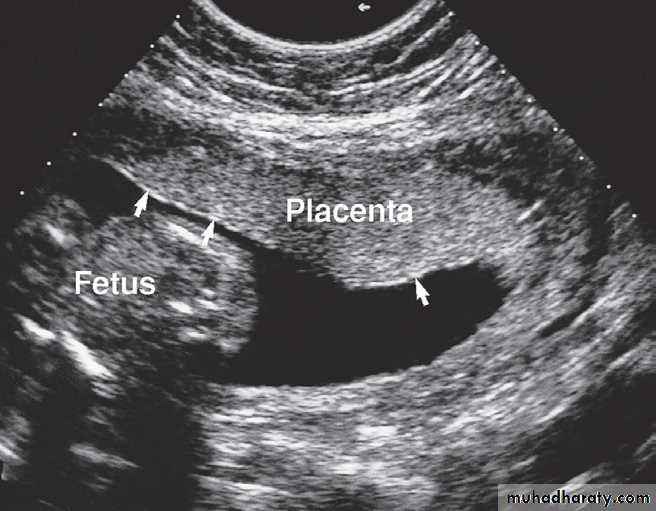

After the first trimester, trans abdominal ultrasound is used to assess fetal maturity by measuring both the biparieta diameter of the fetal head and the femur length, both of which can be precisely defined. By comparing the measurements with a standard growth chart, an estimate of gestational age can be obtained. Using this method, dating is most accurate between 18 and 20 weeks. This is also a suitable time to identify fetal abnormalities.Placental imaging

The placenta is easily evaluated sonographically as well as on MRI . By the ninth week, it is seen as a welldefined intrauterine structure lining the inner wall of a portion of the uterine cavity. Abnormalities related to the placenta may be diagnosed on ultrasound, including placental haemorrhage and placenta praevia, a condition in which the placenta remains positioned over the lower uterine segment after the 36th week of pregnancy.Fetal death